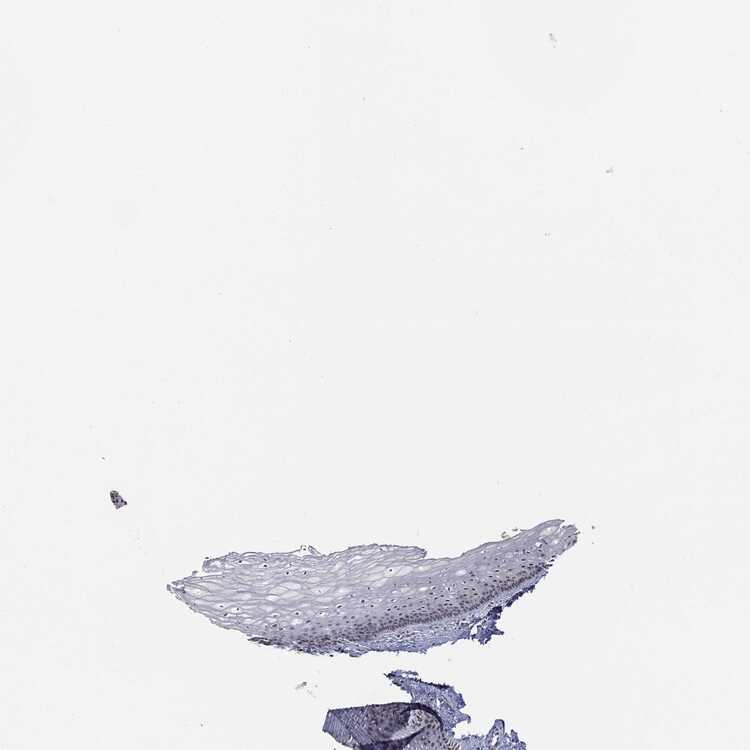

TISSUE PRIMARY DATA VAGINA Show tissue menu

VAGINA - Antibody stainingi

Antibody staining in the annotated cell types in the current human tissue is reported as not detected, low, medium, or high, based on conventional immunohistochemistry profiling in selected tissues. This score is based on the combination of the staining intensity and fraction of stained cells.

Each image is clickable and will lead to virtual microscopy that enables deeper exploration of all samples and also displays staining intensity scores, fraction scores and subcellular localization as well as patient and tissue information for each sample.

Antibody HPA011271Antibody HPA011272Antibody CAB013023Antibody CAB035987Antibody CAB058693Antibody CAB080415

Squamous epithelial cells LowMediumHighHighHighLow